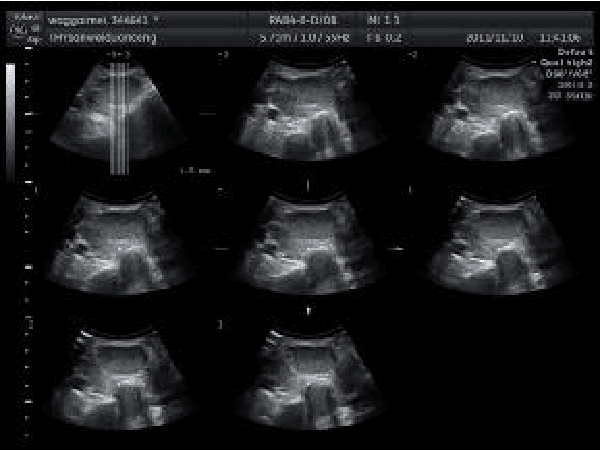

The incidence of thyroid nodule is very high and generally increases with the age. Thyroid nodule may presage the emergence of thyroid cancer. The thyroid nodule can be completely cured if detected early. Fine needle aspiration cytology is a recognized early diagnosis method of thyroid nodule. There are still some limitations in the fine needle aspiration cytology, and the ultrasound diagnosis of thyroid nodule has become the first choice for auxiliary examination of thyroid nodular disease. If we could combine medical imaging technology and fine needle aspiration cytology, the diagnostic rate of thyroid nodule would be improved significantly. The properties of ultrasound will degrade the image quality, which makes it difficult to recognize the edges for physicians. Image segmentation technique based on graph theory has become a research hotspot at present. Normalized cut (Ncut) is a representative one, which is suitable for segmentation of feature parts of medical image. However, how to solve the normalized cut has become a problem, which needs large memory capacity and heavy calculation of weight matrix. It always generates over segmentation or less segmentation which leads to inaccurate in the segmentation. The speckle noise in B ultrasound image of thyroid tumor makes the quality of the image deteriorate. In the light of this characteristic, we combine the anisotropic diffusion model with the normalized cut in this paper. After the enhancement of anisotropic diffusion model, it removes the noise in the B ultrasound image while preserves the important edges and local details. This reduces the amount of computation in constructing the weight matrix of the improved normalized cut and improves the accuracy of the final segmentation results. The feasibility of the method is proved by the experimental results.